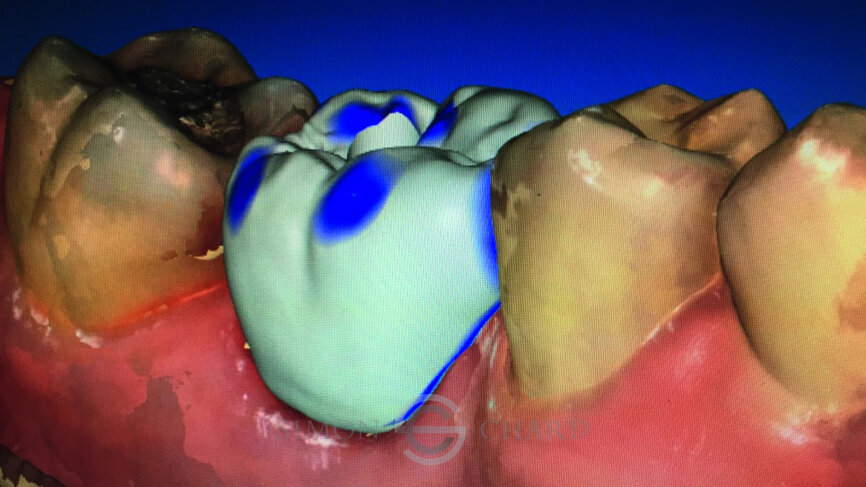

Following digital intraoral scanning (DIOS) of the opposing arch, working arch and buccal bite, a digital design was created using the biogeneric individual design mode. In this design mode on the CEREC Omnicam, the software evaluates the other teeth captured in the DIOS and tries to recreate what it believes to be the closest match to the original missing tooth (Figs. 9–11).

This tooth design is then positioned digitally within an e.max meso block. This meso block has a predetermined hole within it that acts as the access hole for the screw-retained crown, as well as the orifice into which a TiBase will be bonded (Fig. 12).